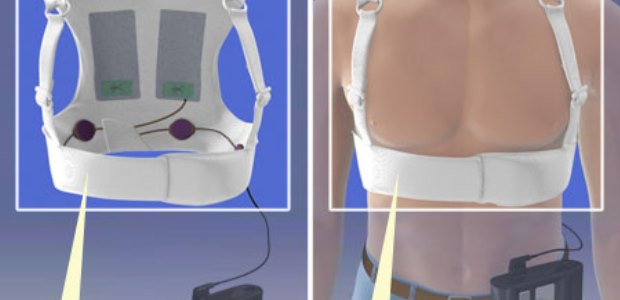

"Doctors now have important information that may help them safely prescribe this life-saving device to young patients who may benefit from the device," said Dr. Vasum Peiris, M.D., MPH, chief medical officer of Pediatrics and Special Populations in FDA's Center for Devices and Radiological Health.